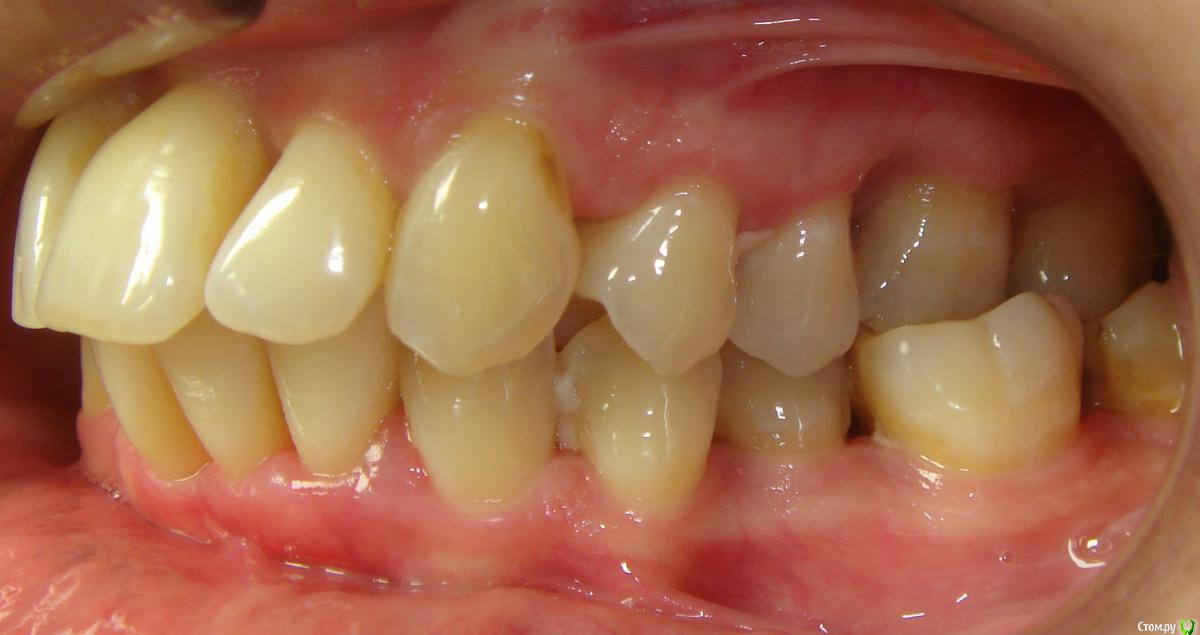

Opdihatop Опубликовано 9 мая, 2016 Поделиться Опубликовано 9 мая, 2016 (изменено) Здравствуйте, коллеги! Хотел бы представить вашему вниманию вот такой вот случай и спросить совета. В принципе, по окклюзии ничего особенного по лечению нет, но вот проблемы с пародонтом (на КТ по кости все заметно хуже, чем на орто), делают невозможным все, продуманные мной варианты. Может у кого-то было что-то подобное? Может поделитесь советом, а то помочь человеку надо, а я в тупике. Буду заранее очень благодарен за помощь! Изменено 9 мая, 2016 пользователем Opdihatop Ссылка на комментарий

Opdihatop Опубликовано 11 мая, 2016 Автор Поделиться Опубликовано 11 мая, 2016 Я думал сделать тут SARPE и поставить небный расширитель, который крепится не к зубам, а к кости под слизистой (не помню, как называется), на н/ч планировал удалять один резец и работать на самолигах, но вот боюсь еще большей потери кости. А Вы как думаете? Ссылка на комментарий

Opdihatop Опубликовано 12 мая, 2016 Автор Поделиться Опубликовано 12 мая, 2016 (изменено) И что, кросс тяги и простое расширение на самолигах не вызовет, при таком пародонте, полного разрушения системы (я про кость)? Изменено 12 мая, 2016 пользователем Opdihatop Ссылка на комментарий

Opdihatop Опубликовано 13 мая, 2016 Автор Поделиться Опубликовано 13 мая, 2016 (изменено) Попова послушать лично не смогу. Я живу в Украине и он к нам, по понятным причинам, не приезжает (был когда-то на конгрессе, но там лекция по минивинтам была). 1) По ТРГ про второй класс я с Вами абсолютно согласен. Здесь главное, что волнует пациентку, это создание места под 13 зуб. Да, она согласна корректировать все остальные проблемы, но не пойдет на лечение, если "ее" цель не будет достигнута. И да, я понимаю, что идеала тут достичь у меня не получится.2) Так уж сложилось, что кросс-эластиками я не так уж много работал, как то пациенты не подворачивались. По-этому позвольте в связи с этим вопрос: а не навредит ли нам тут вестибулярный наклон верхних моляров, который несомненно возникнет за счет тяги (они наклонены орально незначительно)? Да, я понимаю, что и нижние наклонятся орально, но все же.3) Почему Вы против, пусть даже не сарпе, так хоть послабления небного шва в этом случае? С трудом верится, что в этом возрасте, пусть даже на самолигах, получится получить стабильное расширение.И последнее 4) Я встречал в литературе успешное применение, при подобном пародонте, дистализации на в/ч при непрямом анкораже на м/и. Подобное лечение (с нормальной костью) неоднократно производил и успешно. Как Вы считаете, рискнуть или успех маловероятен? Простите за сумбур, просто много мыслей в голове. Изменено 13 мая, 2016 пользователем Opdihatop Ссылка на комментарий

Yana guapa Опубликовано 13 мая, 2016 Поделиться Опубликовано 13 мая, 2016 1) Здесь главное, что волнует пациентку, это создание места под 13 зуб. Да, она согласна корректировать все остальные проблемы, но не пойдет на лечение, если "ее" цель не будет достигнута. И да, я понимаю, что идеала тут достичь у меня не получится. под 1.3. зуб место создадите без проблем. Но если Ваша пациентка мечтает о голливуде (может еще и о новом пародонте?) , то лучше ее вообще не брать. Пусть радуется хоть тому, что вообще можно слепить. 2) Так уж сложилось, что кросс-эластиками я не так уж много работал, как то пациенты не подворачивались. По-этому позвольте в связи с этим вопрос: а не навредит ли нам тут вестибулярный наклон верхних моляров, который несомненно возникнет за счет тяги (они наклонены орально незначительно)? Да, я понимаю, что и нижние наклонятся орально, но все же. у вас не будет чистого вестибулярного наклона верхних моляров, потому что помимо кросс-эластиков у вас будут хорошие расширяющие дуги, придающие нужную форму зубному ряду. плюс кросс-тяги. и конечно хорошее разобщение. 3) Почему Вы против, пусть даже не сарпе, так хоть послабления небного шва в этом случае? С трудом верится, что в этом возрасте, пусть даже на самолигах, получится получить стабильное расширение. если Вам там хочется поставить RPE поставьте) но вы всегда можете это успеть сделать, в случае неудачи кросс тяг. заранее обговаривается. (тем более это дополнительные финансовые траты) 4) Я встречал в литературе успешное применение, при подобном пародонте, дистализации на в/ч при непрямом анкораже на м/и. Подобное лечение (с нормальной костью) неоднократно производил и успешно. Как Вы считаете, рискнуть или успех маловероятен? а что Вы дистализировать здесь хотите? Ссылка на комментарий